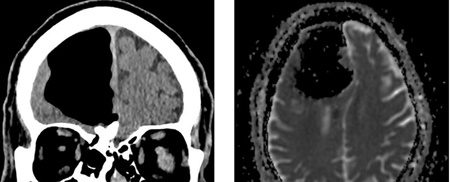

بر اساس گزارش ساینس الرت، تصاویر سی‌تی‌اسکن مغز این بیمار نشان داد، بخش بزرگی از لوب پیشانی راست مغز مرد ناپدید شده‌ است.

نتیجه سی‌تی‌اسکن گیج‌کننده بود، حفره‌ای بزرگ و سیاه به وسعت 9 سانتیمتر در لوب پیشانی سمت راست مرد دیده می‌شد. در مرحله بعدی مغز مرد با دستگاه MRI مورد بررسی قرار گرفت و پزشکان دریافتند ماده مغزی در جمجمه بیمار ناپدید نشده‌است، بلکه درون جمجمه‌اش حفره‌ای از هوا به نام پنوماتوکوئل ایجاد شده‌بود که معمولا در بیمارانی دیده می‌شود که دچار آسیب‌دیدگی صورت یا عفونت تنفسی شده‌اند یا در جمجمه آنها جراحی انجام شده‌ است.

اما هیچ‌یک از این عوامل در این بیمار به ایجاد این پنوماتوکوئل بزرگ منجر نشده‌ بود. پزشکان همچنین در استخوان اتموئید مغز مرد،‌استخوانی که حفره تنفسی را از مغز جدا می‌کند، نوعی تومور خوش‌خیم پیدا کردند. این بخش آسیب‌دیده استخوانی باعث شده بود تا هوا به درون جمجمه نشت کرده و پدیده ای به نام تاثیر لوله یک‌طرفه ایجاد کند.